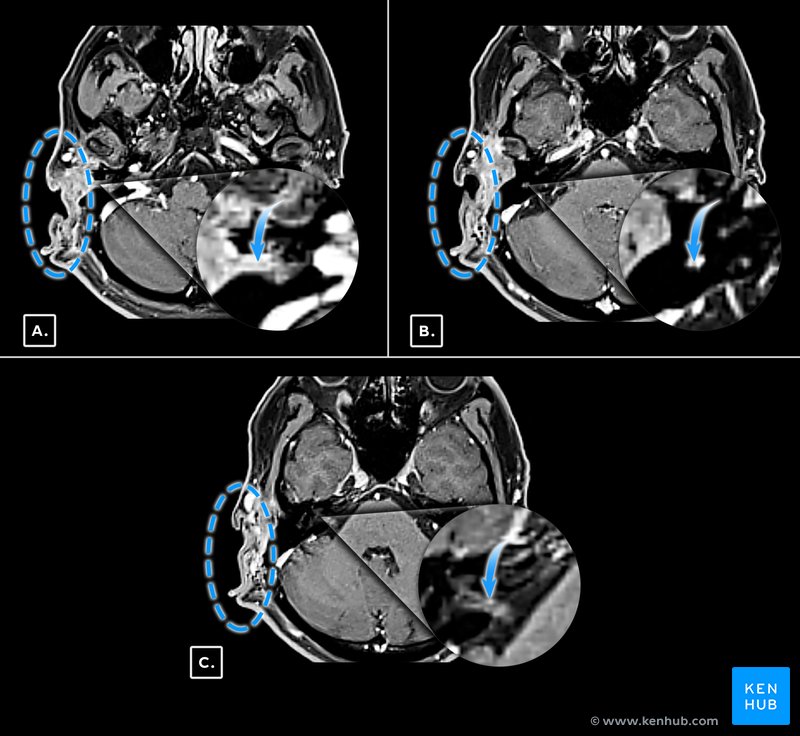

MRI demonstrated remaining periauricular subcutaneous lesions that appeared to extend medially from the stylomastoid foramen into the intratemporal canal, facial nerve canal to the internal auditory canal (Figure 2).

MRI with contrast also showed subcutaneous lesions from the enlarged stylomastoid foramen and also an enlarged facial canal (Figure 3).